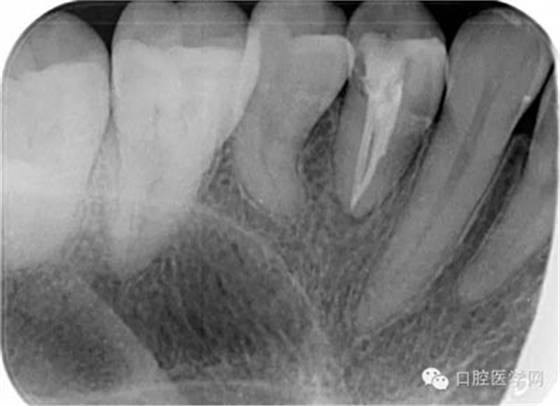

第七步:根管充填 使用對(duì)應(yīng)錐度及號(hào)數(shù)的牙膠尖充填。